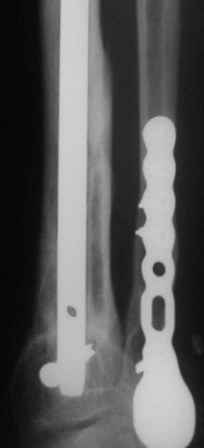

А я бы хотел еще раз подчеркнуть ключевую роль вмешательства на малоберцовой кости в подобной ситуации. В приведенном примере при открытом переломе произошла потеря большого фрагмента большеберцовой кости. Фиксация интрамедуллярным гвоздем с одним блокирующим винтом проксимально и одним дистально. Плюс стабильный остеосинтез малоберцовой. Консолидация за три месяца без  костной пластики в условиях ранней нагрузки.